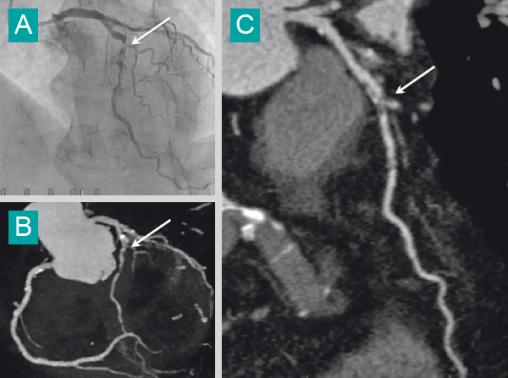

On objective sur les reconstructions 3D (B) et curviligne (C) une sténose serrée de l'IVA, retrouvée sur la coronarographie (A).